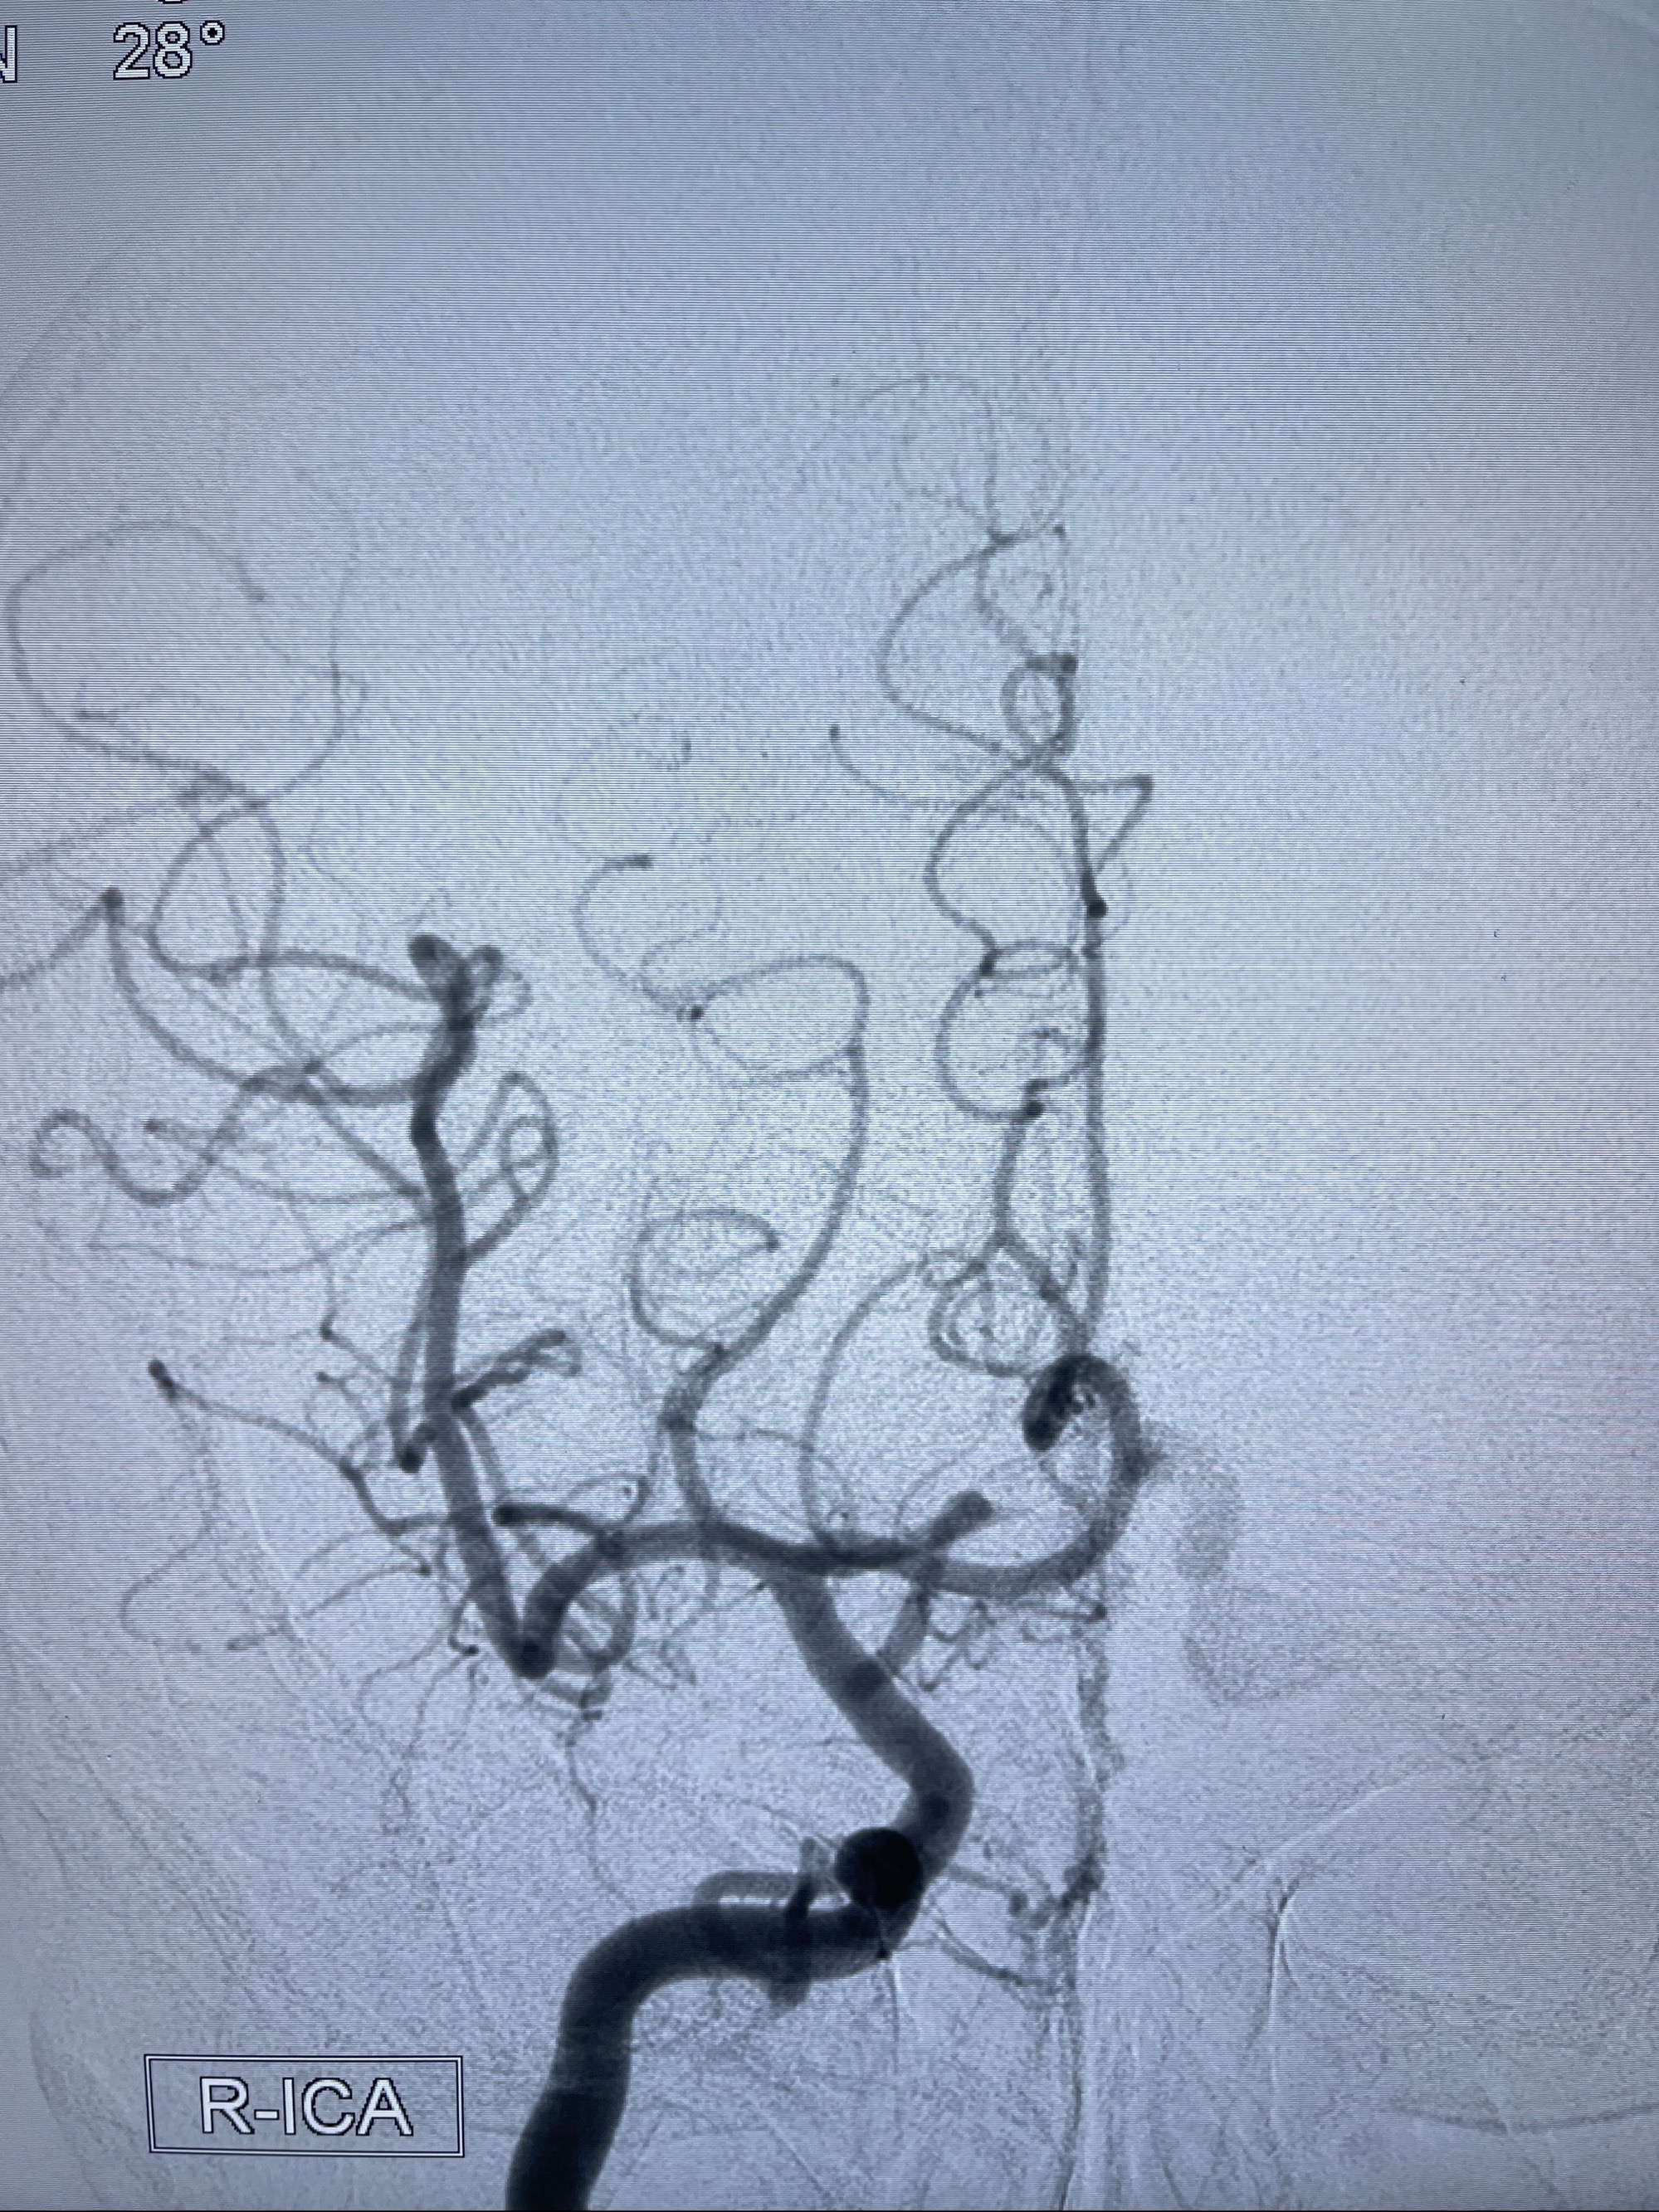

2023年8月21日]景德镇市第一人民医院脑血管造影检查,提示:主动脉弓、双侧颈总动脉、锁骨下动脉造影未见异常,左侧大脑前动脉静脉瘘。

2023-09-13全脑血管造影:前颅底硬脑膜动静脉瘘,供血动脉为双侧胼周动脉、眼动脉脑膜支,静脉向上矢状窦方向引流